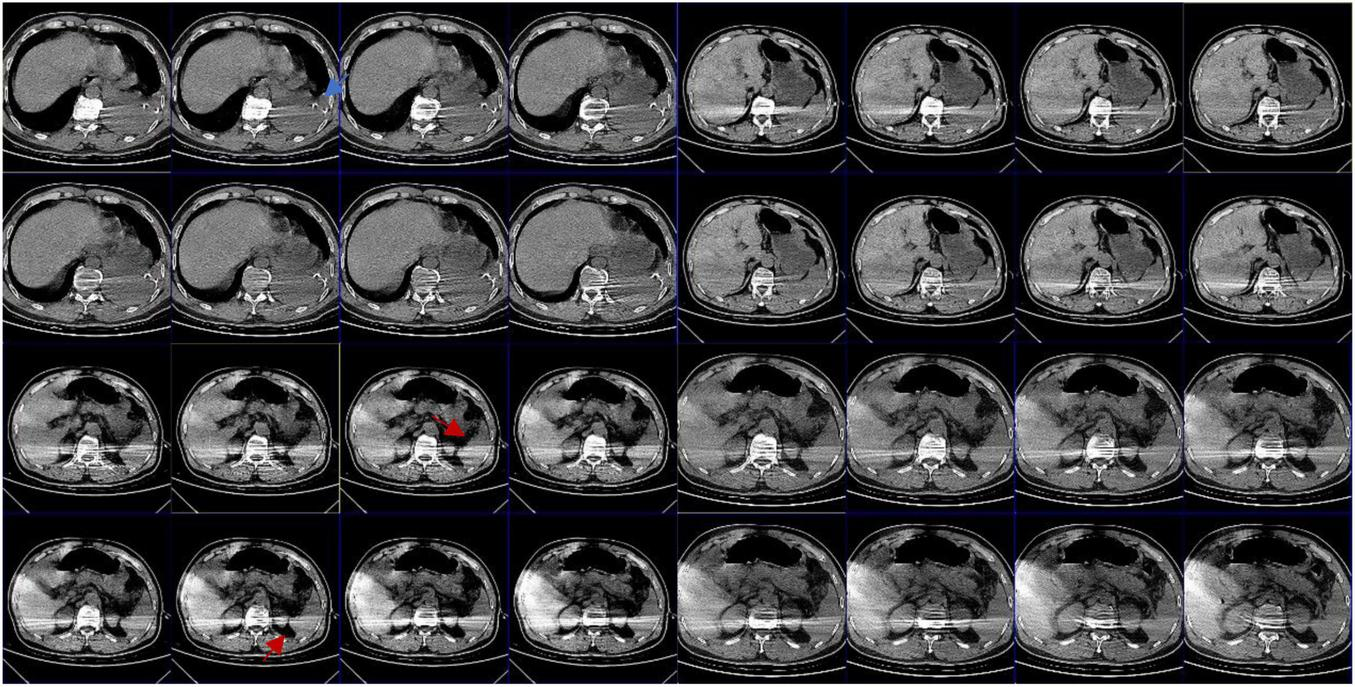

FIGURE 5

Abdominal CT: the blue arrow shows intrathoracic drain; the red arrow shows that there appears to be exudate around the spleen; the splenic hilum appears to be intact.